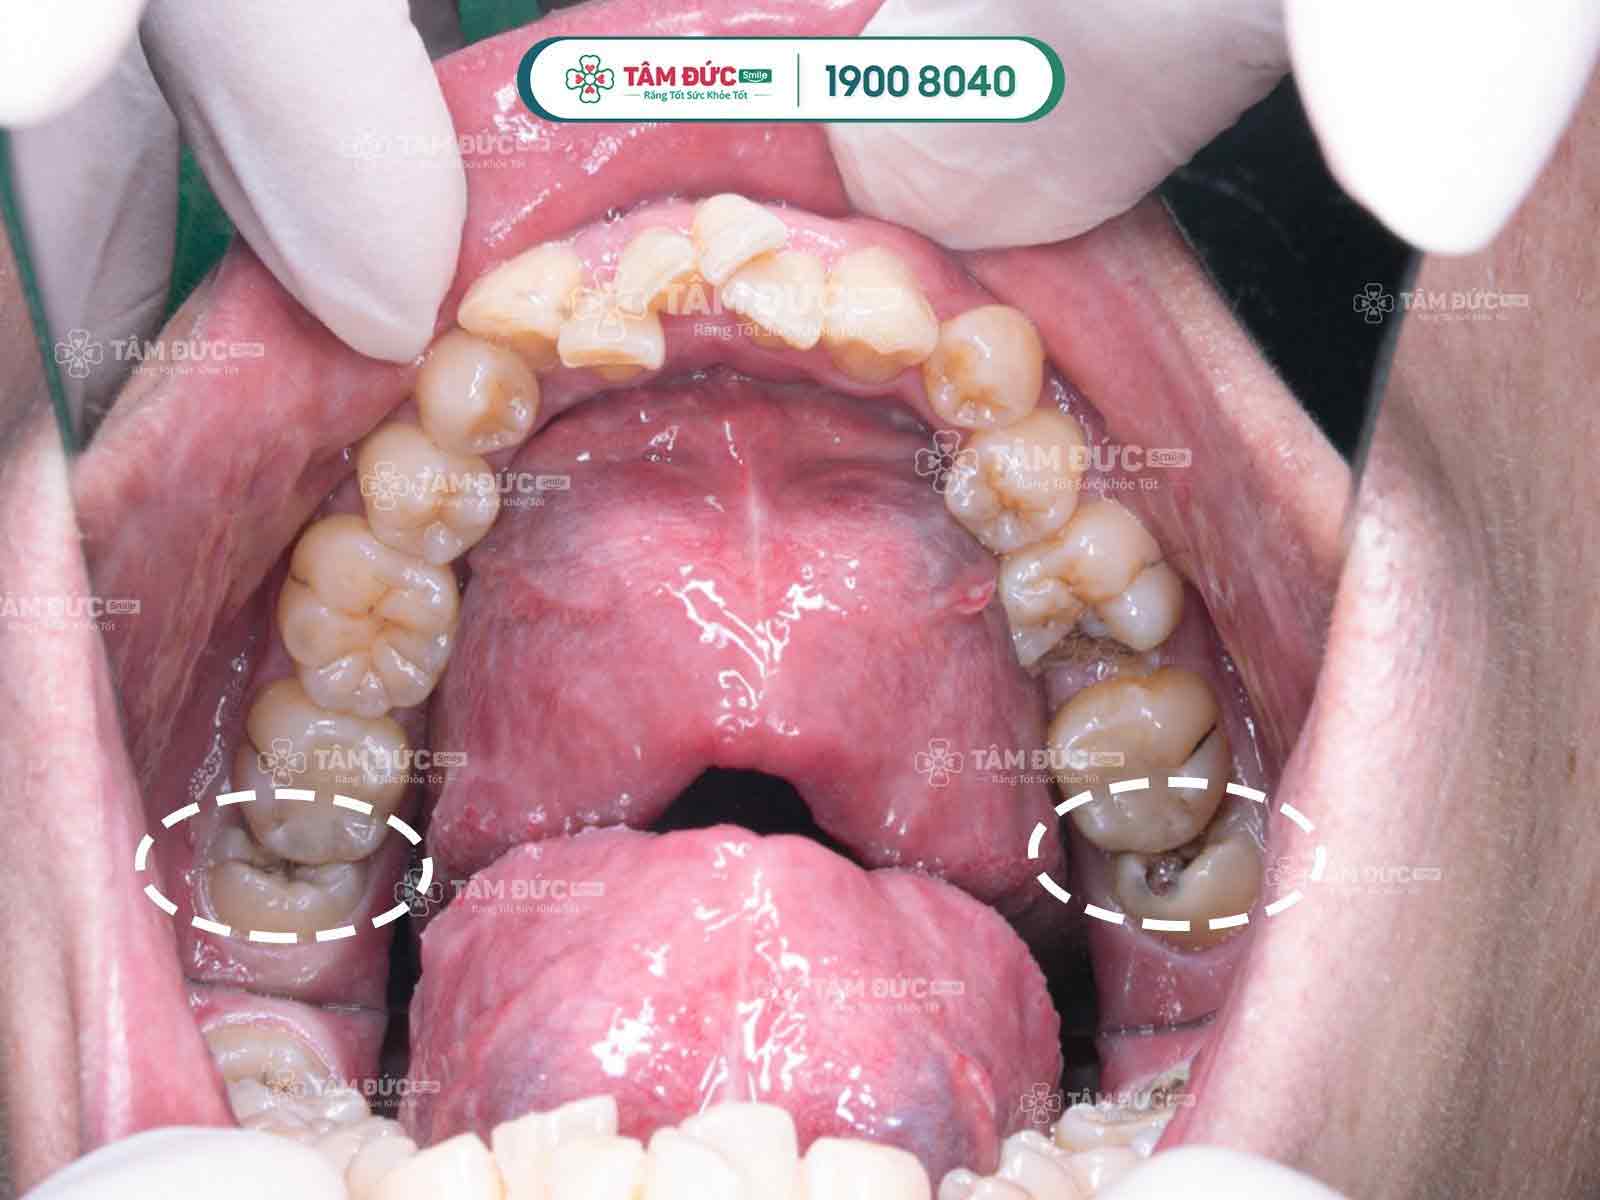

Khi răng khôn mọc nghiêng thức ăn dễ kẹt vào kẽ răng, điều này khiến việc vệ sinh răng miệng gặp khó khăn, lâu dần tạo điều kiện để vi khuẩn sinh sôi, phát triển đục khoét vào men răng, dẫn đến tình trạng sâu răng, có thể gây viêm nhiễm làm răng khôn đau nhức dữ dội.

Răng khôn mọc ngầm thường có hiểu hiện làm nướu sưng tấy, viêm đỏ, khó há miệng. Vì xương hàm không có đủ vị trí nên nó sẽ đâm sang răng bên cạnh, nó sẽ làm chiếc răng khỏe mạnh kế bên dần bị tiêu hủy, lung lay có thể dẫn đến sâu, nặng hơn nó sẽ khiến chiếc răng này bị xô đẩy chèn ép và rụng đi gây mất răng. Răng khôn mọc lệch, ngầm thường gây ra những cơn đau răng khôn âm ỉ kéo dài trong khoản 2 tới 3 ngày.